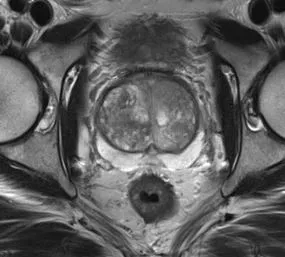

Meyer, A; Mehrtash, A; Rak, M; Bashkanov, O; Langbein, B; Ziaei, A; Kibel, A; Tempany, C; Hansen, C; Tokuda, J

Domain adaptation for segmentation of critical structures for prostate cancer therapy Journal Article

In: Scientific Reports, vol. 11, no. 1, pp. 11480, 2021, ISSN: 2045-2322.

abstract = {Preoperative assessment of the proximity of critical structures to the tumors is crucial in avoiding

unnecessary damage during prostate cancer treatment. A patient-specific 3D anatomical model

of those structures, namely the neurovascular bundles (NVB) and the external urethral sphincters

(EUS), can enable physicians to perform such assessments intuitively. As a crucial step to generate a

patient-specific anatomical model from preoperative MRI in a clinical routine, we propose a multi-class

automatic segmentation based on an anisotropic convolutional network. Our specific challenge is to

train the network model on a unique source dataset only available at a single clinical site and deploy it

to another target site without sharing the original images or labels. As network models trained on data

from a single source suffer from quality loss due to the domain shift, we propose a semi-supervised

domain adaptation (DA) method to refine the model’s performance in the target domain. Our DA

method combines transfer learning and uncertainty guided self-learning based on deep ensembles.

Experiments on the segmentation of the prostate, NVB, and EUS, show significant performance gain

with the combination of those techniques compared to pure TL and the combination of TL with simple

self-learning ( p < 0.005 for all structures using a Wilcoxon’s signed-rank test). Results on a different

task and data (Pancreas CT segmentation) demonstrate our method’s generic application capabilities.

Our method has the advantage that it does not require any further data from the source domain,

unlike the majority of recent domain adaptation strategies. This makes our method suitable for clinical

applications, where the sharing of patient data is restricted.},

keywords = {},